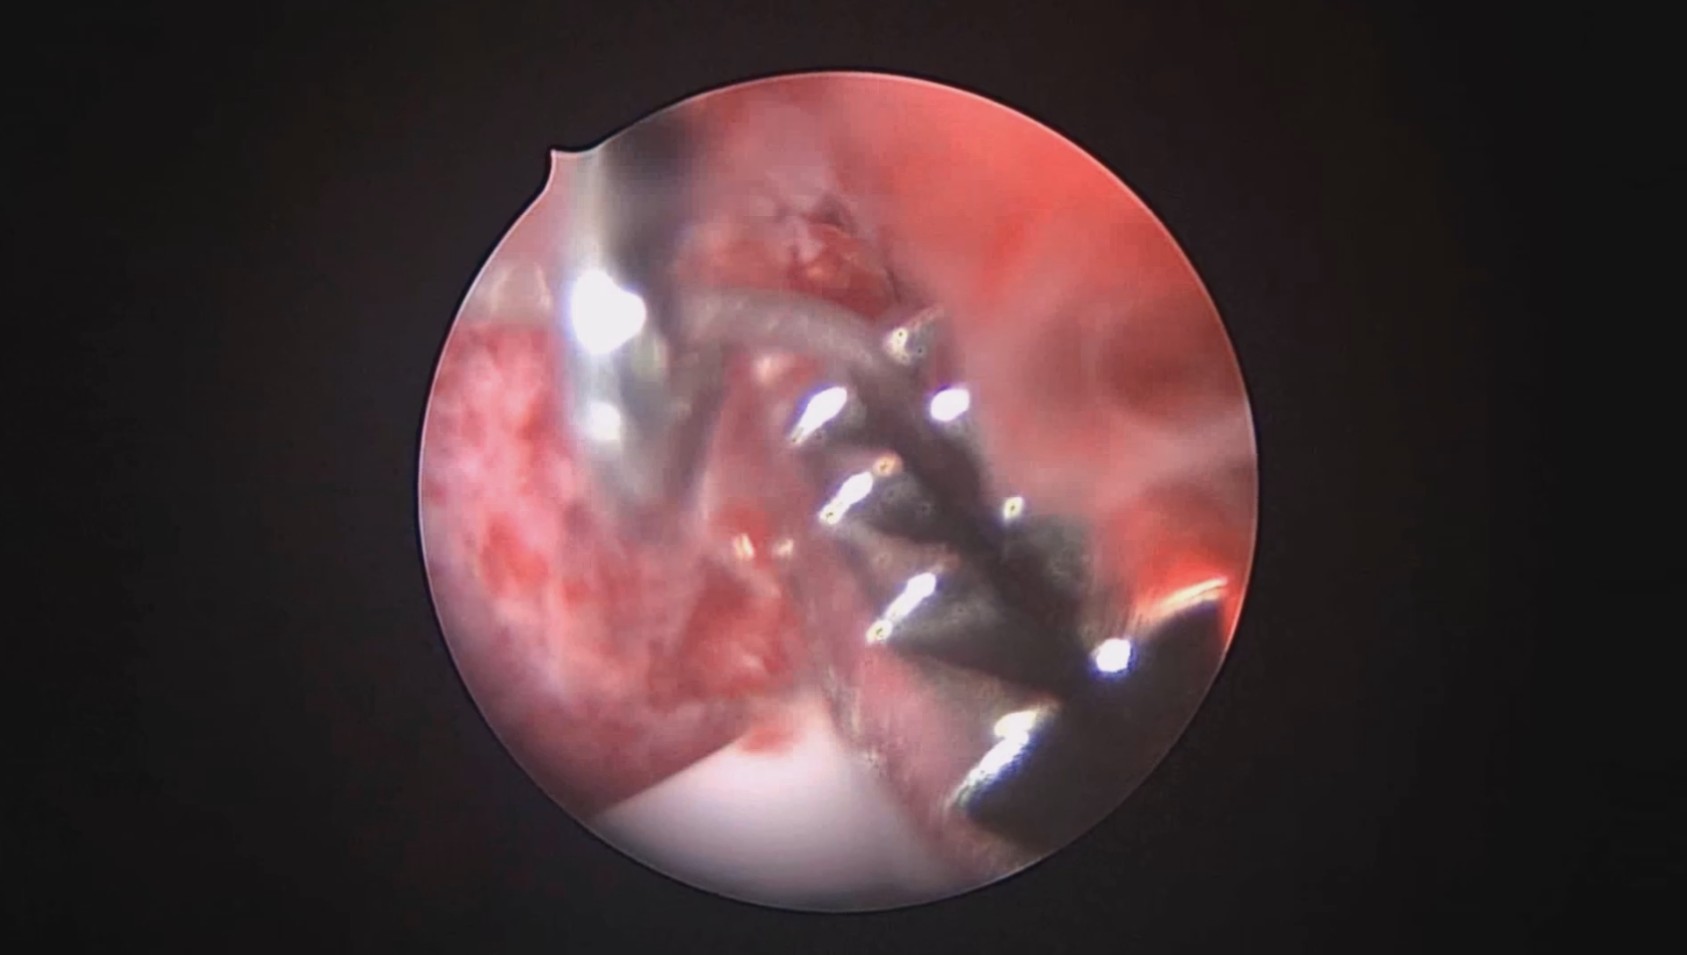

宫腔镜下节育器固定病例6

患者41岁,G4P2,顺产2次。因异常子宫出血于2023年12月在外院行宫腔镜检查,取内膜病检为增生晚期及分泌早期宫内膜组织,另见宫内膜息肉,术后药物治疗效果不佳,月经周期不规律。本次阴道不规则流血10+天,量多就诊。宫腔镜下尝试线结扣宫底锚定曼月乐,将结推人宫底肌层很困难,最后采用不锈钢挂钩固定。用曼月乐尾丝连接环与不锈钢挂钩,将挂钩插入宫底肌层,异物钳原位固定曼月乐,退出宫腔镜,结束手术。术后患者未回院复查节育环位置。